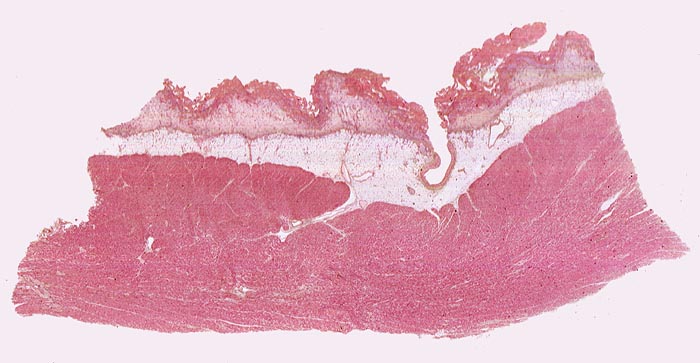

fibrinöse Perikarditis

Perikard

Das Epikard (innere Schicht des Perikardblattes) ist bedeckt von einer zottigen Fibrinschicht. Gegen innen folgt eine Granulationsgewebsschicht, welche das Fibrin organisiert, gefolgt vom epikardialen Fettgewebe und vom Myokard. Ehemalige Lokalisation der Perikardoberfläche (einschichtiges Mesothel). Koronararterienast im epikardialen Fettgewebe.

Patientin verstorben in Urämie.